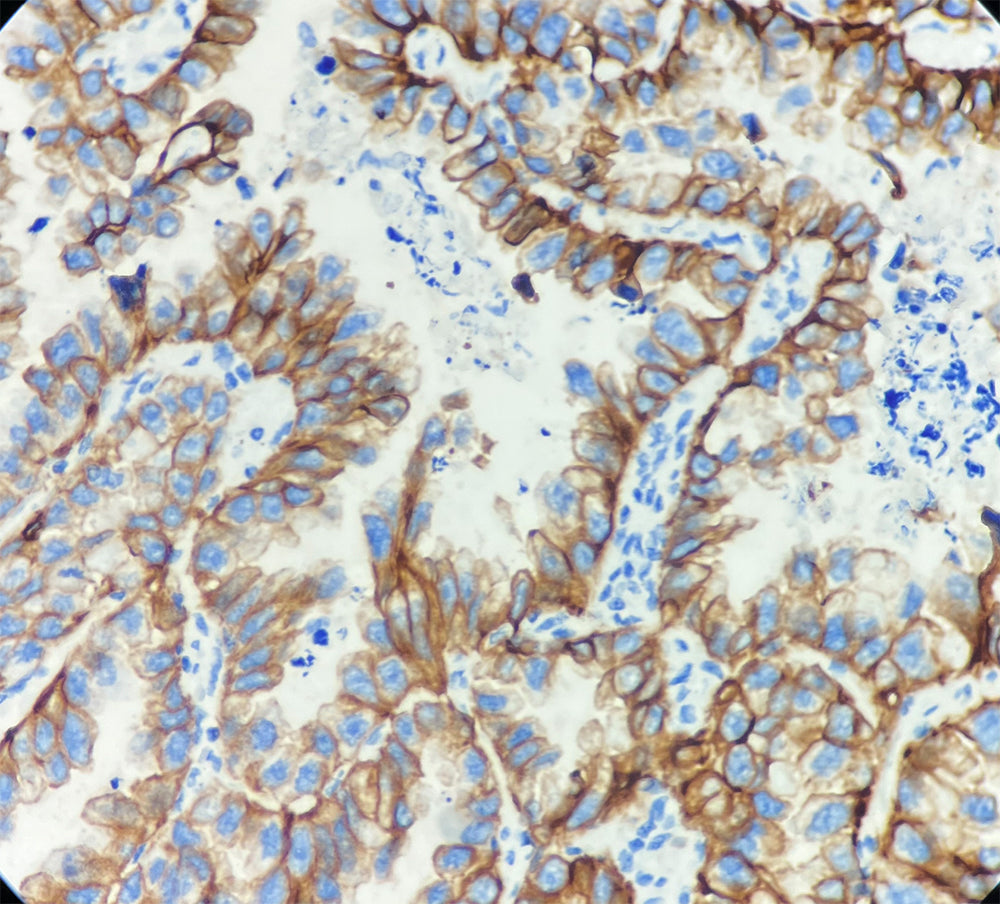

Cytokératine CAM5.2

CAM5.2 est une cytokératine également connue sous le nom de kératine de bas poids moléculaire (48 kDa et 52 kDa), correspondant aux numéros 7 et 8 de la classification de Moll. Elle est spécifiquement exprimée dans l’épithélium glandulaire, mais absente des cellules squameuses stratifiées et de l’urothélium.

① Son rôle de marqueur spécifique de l’épithélium glandulaire, permettant de distinguer efficacement les adénocarcinomes (positifs) des carcinomes épidermoïdes (négatifs) ;

Il convient de noter que l’anticorps CAM5.2 peut présenter une réactivité croisée avec certains carcinomes épidermoïdes peu différenciés, ce qui nécessite une interprétation intégrée avec d’autres marqueurs.

Contrôle positif : Tissu d’adénocarcinome pulmonaire